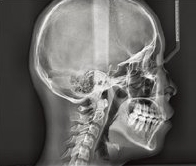

CT를 이용한 진단

CT를 통해 구강 전반은 물론 얼굴뼈 부위까지 광범위한 진단을 통해서 육안으로는 파악이 불가한 부분까지 볼 수 있습니다.

구강내의 구조나 뼈의 양, 상악동 수술여부 등 다양한 부분을 체크할 수 있어 의료진이 올바른 진단을 내리는데 도움을 줍니다.

CT진단을 활용하여 구강상태를 면밀하게 살펴보고 임플란트를 식립합니다.